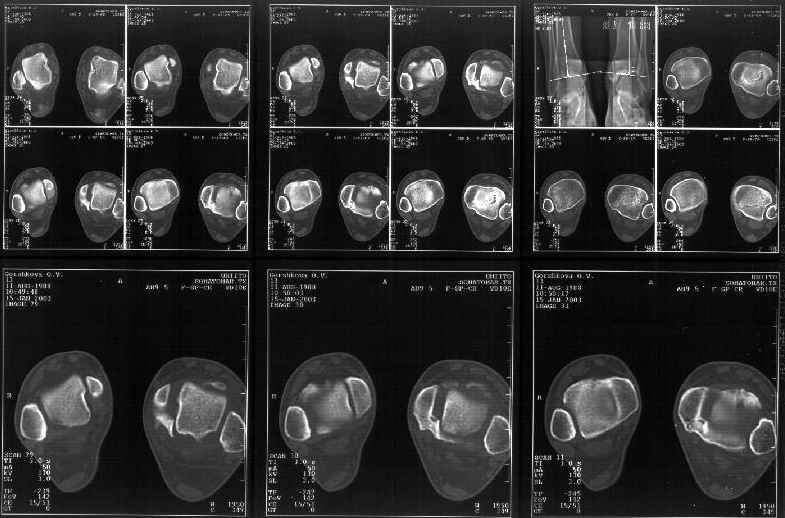

Сегодня пациентке сделали сравнительную КТ. А ксиальные и Фронтальные срезы приложены. Ваше мнение?

Фронтальные

Аксиальные

Спасибо за КТ -она изумительная. К сожалению, я по дороге на врачебный викенд на Мёртвом море и не смогу подготовить комментарий и схемку до 19.01.03 Помоему, результат КТ даёт чёткую возможность красивой и эффективной помощи.

Отправитель: Й. Воск 19 Январь 2003, 22:50

На КТ я попытался изобразить скромными своими способностями (А)- место перелома, (С)- нормальный суставной зазор меж тараном и тремя его маллеолами. (В)- образовавшийся в результате перелома широкий раза в три зазор, позволяющий, по-моему, сублюксацию тарана при ходьбе. В свете данных КТ, критически важных, я бы предложил вертикальную остеотомию места перелома

задне-внутренним подходом и фиксацию мед. маллеола прижатым к тарану с помощью тонкого compression screw. После этого гипсовый сапожок и немедленное расхаживание ноги.